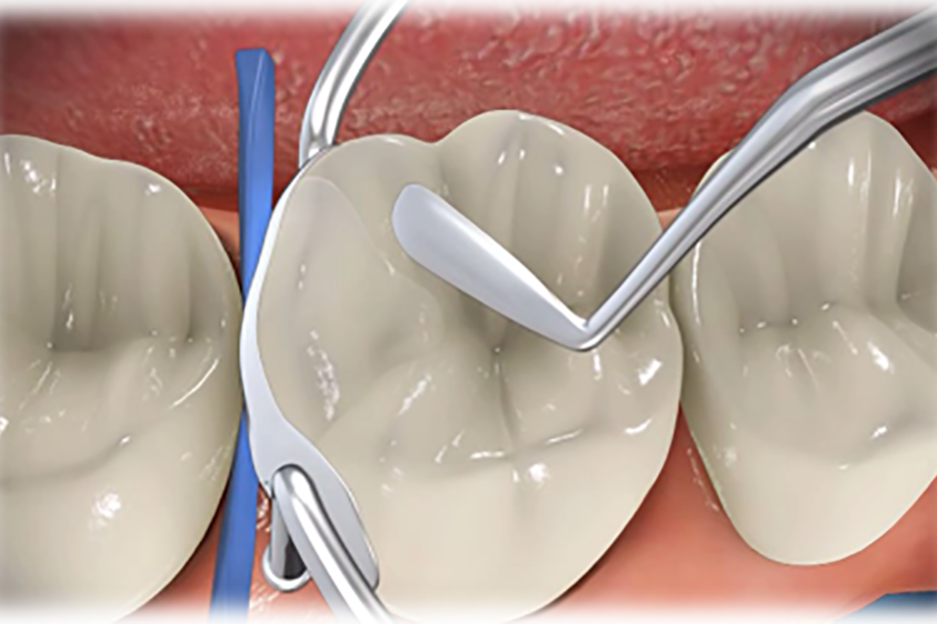

La odontología conservadora y restauradora nos permite prevenir, detener y curar la caries dental en todas sus fases desde la menor a la mayor destrucción de tejido dentario.

En Dental Marín conseguimos un resultado exitoso mediante la realización de todos los procedimientos adecuados con los mejores materiales y una excelente rehabilitación de la anatomía de cada una de las piezas dentarias.